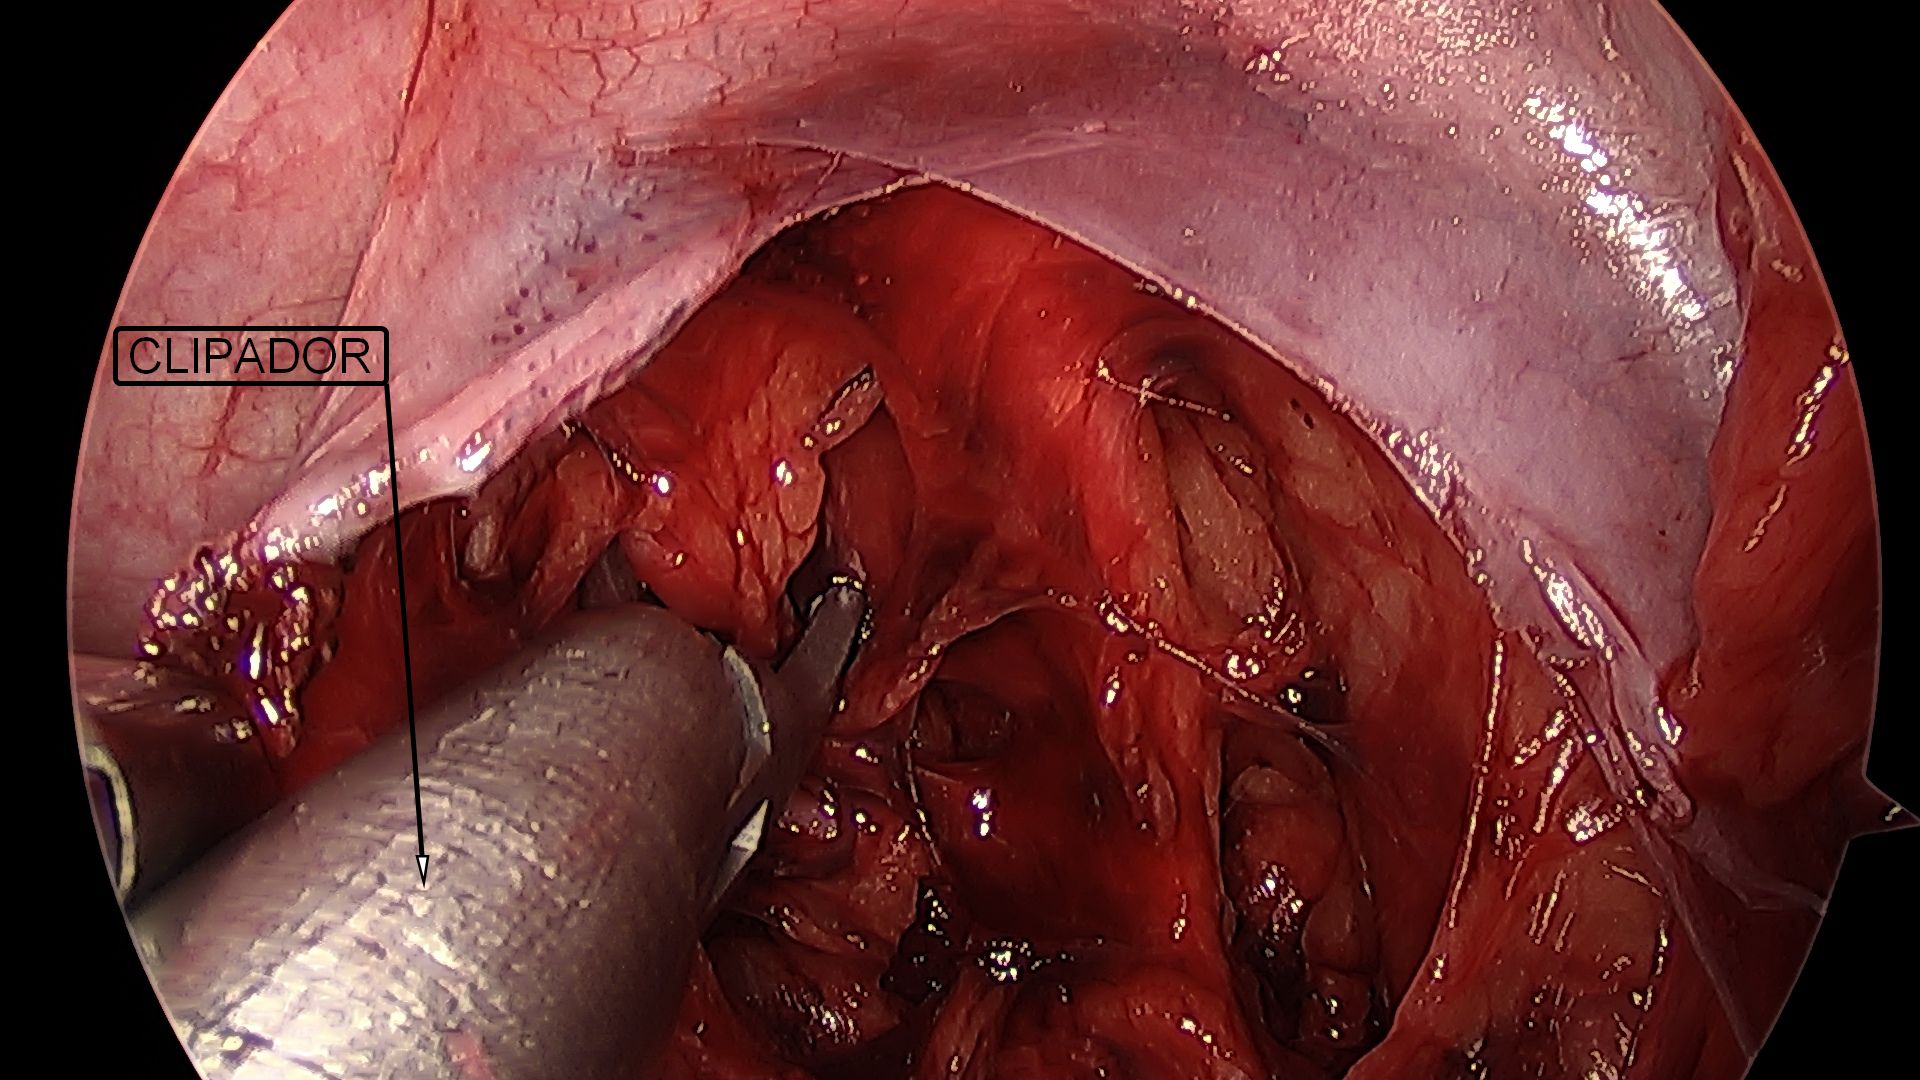

A fecundação do óvulo ocorre na trompa e a partir de então, com os movimentos peristálticos, esse óvulo fecundado é direcionado para o útero, Na gravidez tubária, notamos uma falha nesses movimentos, fazendo com que a gestação se desenvolva no interior da trompa. Com o avançar da gravidez, ocorre a dilatação da trompa, acompanhada de dor importante na parte baixa do abdômen. Eventualmente, essa dilatação ocorre de tal forma que a tuba uterina acaba rompendo (rota) e provocando hemorragia abdominal, exigindo intervenção cirúrgica rápida. A laparoscopia é excelente via de acesso para o tratamento da gravidez tubária.

Ocorre quando um cisto de ovário torce seu pedículo, impedindo a passagem de sangue para o órgão e, consequentemente, causando isquemia do tecido ovariano, associada a dor intensa na parte baixa do abdômen. Caso o diagnóstico seja realizado precocemente, a laparoscopia pode reverter esta torção, preservando o ovário. Em casos de diagnóstico tardio, pode haver necrose do tecido ovariano e o ovário deverá ser retirado pela laparoscopia.

Ocorre quando um cisto de ovário se rompe, provocando dor e, por vezes, hemorragia abdominal. Frequentemente, o tratamento será clínico, ou seja, apenas por observação, com controle da dor e através de exames de sangue. Dependendo da resposta da paciente aos analgésicos, quantidade de sangue livre na cavidade abdominal e intensidade da dor, o tratamento indicado será o cirúrgico, preferencialmente, através da laparoscopia.